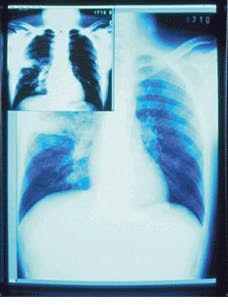

While Metheus uses the PCI bus in its 2k ¥ 2.5k-pixel medical-display controller, Sun`s SBus remains a popular architecture. On its 2048 ¥ 2560 Md5/Sun board, Dome Imaging Systems incorporates an Sbus interface that achieves 20-Mbyte/s sustained throughput, allowing real-time animation of sequential images or fast panning and scrolling of large images (see Fig. 2). Like Metheus` P1540, Dome`s boards incorporate a 10-bit DAC that implements gamma correction while providing a linear, 256-level gray-scale output.

FIGURE 2. SBus burst-mode interface provides 20-Mbyte/s sustained throughput rates for Dome Imaging System`s Md5/Sun. The board supports display resolutions to 2560 ¥ 2048 pixels. A look-up table provides fast window/leveling.